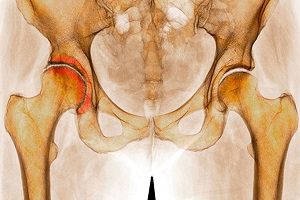

Закрытый перелом правой кости бедра

Перелом со смещением возникает в процессе чрезмерной силовой нагрузки на разные участки конечности. Смещения наиболее характерны для людей в возрасте от 55 лет.

Вызвать смещение могут разные патологии, например, остеопения или остеопороз. Наибольшие повреждения касаются самой кости или её вспомогательных частей.

- С повреждением проксимальной части, симптоматика которого начинается с боли в паху. Второй симптом — возникает эффект «липкой пятки», когда пострадавший в положении лежа не может поднять ногу.